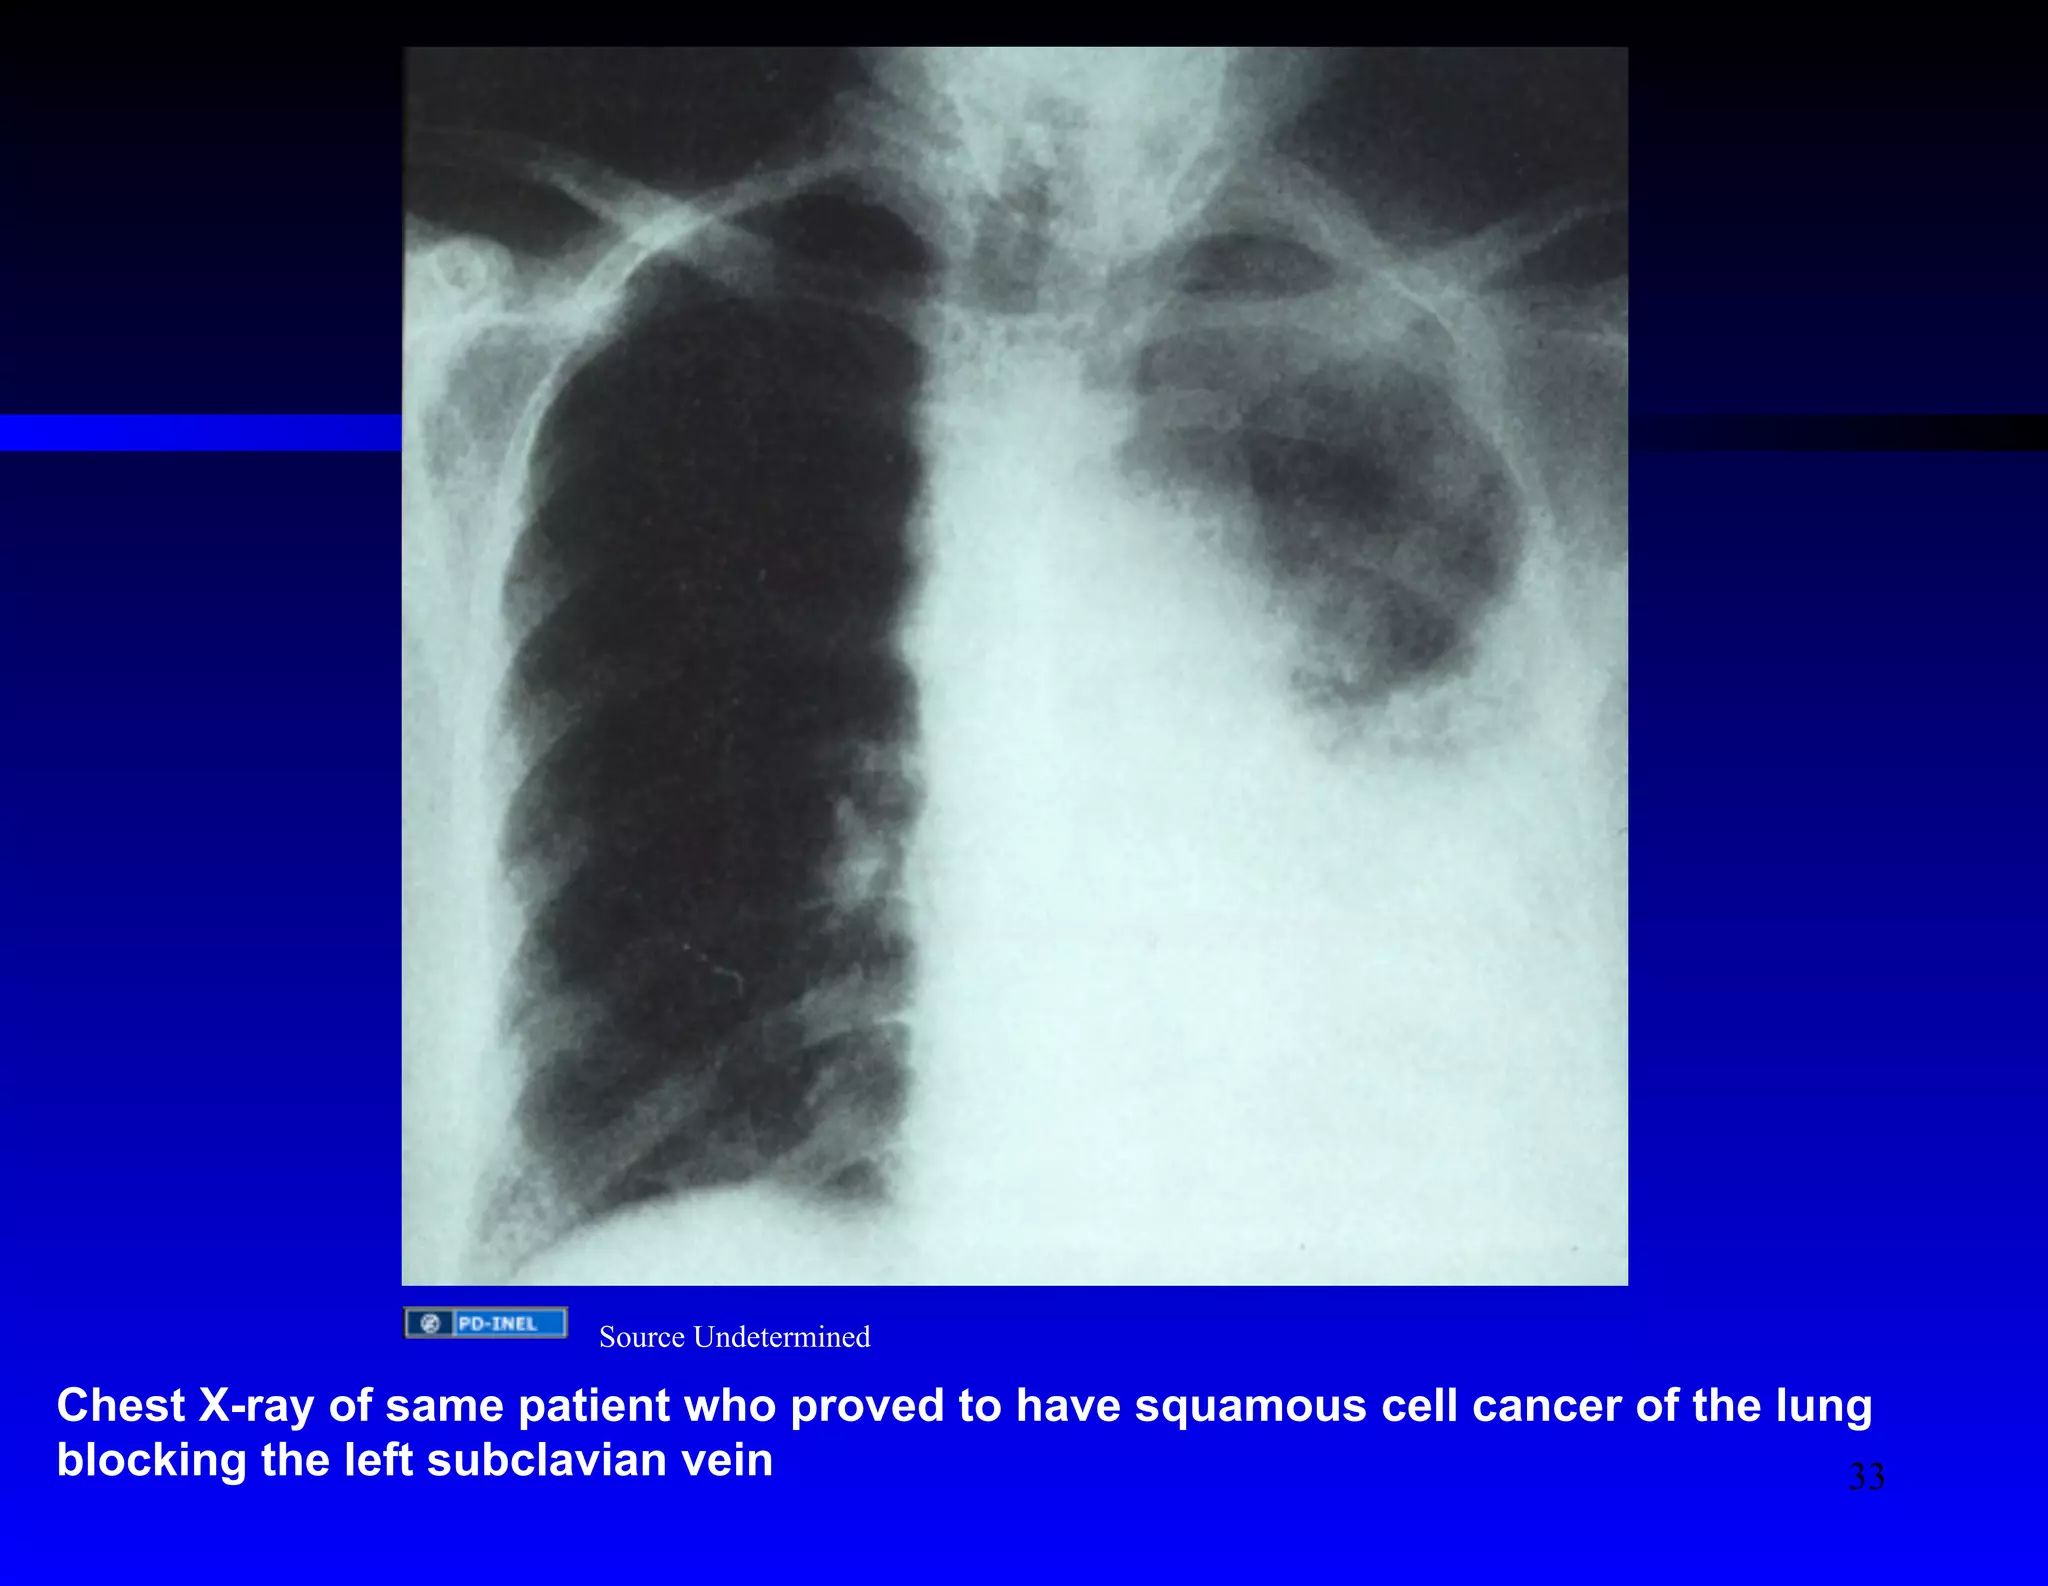

Source Undetermined

Chest X-ray of same patient who proved to have squamous cell cancer of the lung

blocking the left subclavian vein